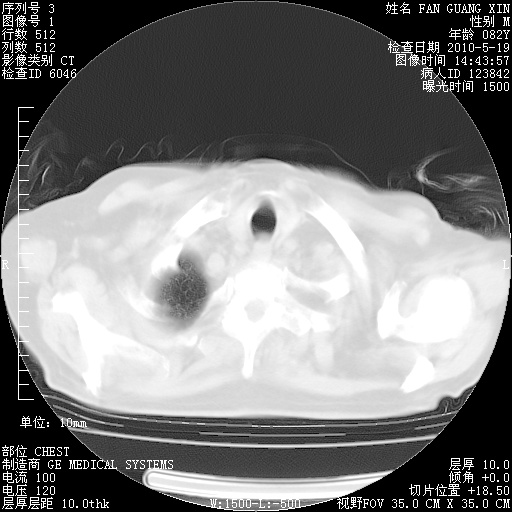

复查肺部CT,明显好转。为什么发热呢?

治疗3周后的肺部CT

治疗3周后的肺部CT纵隔窗